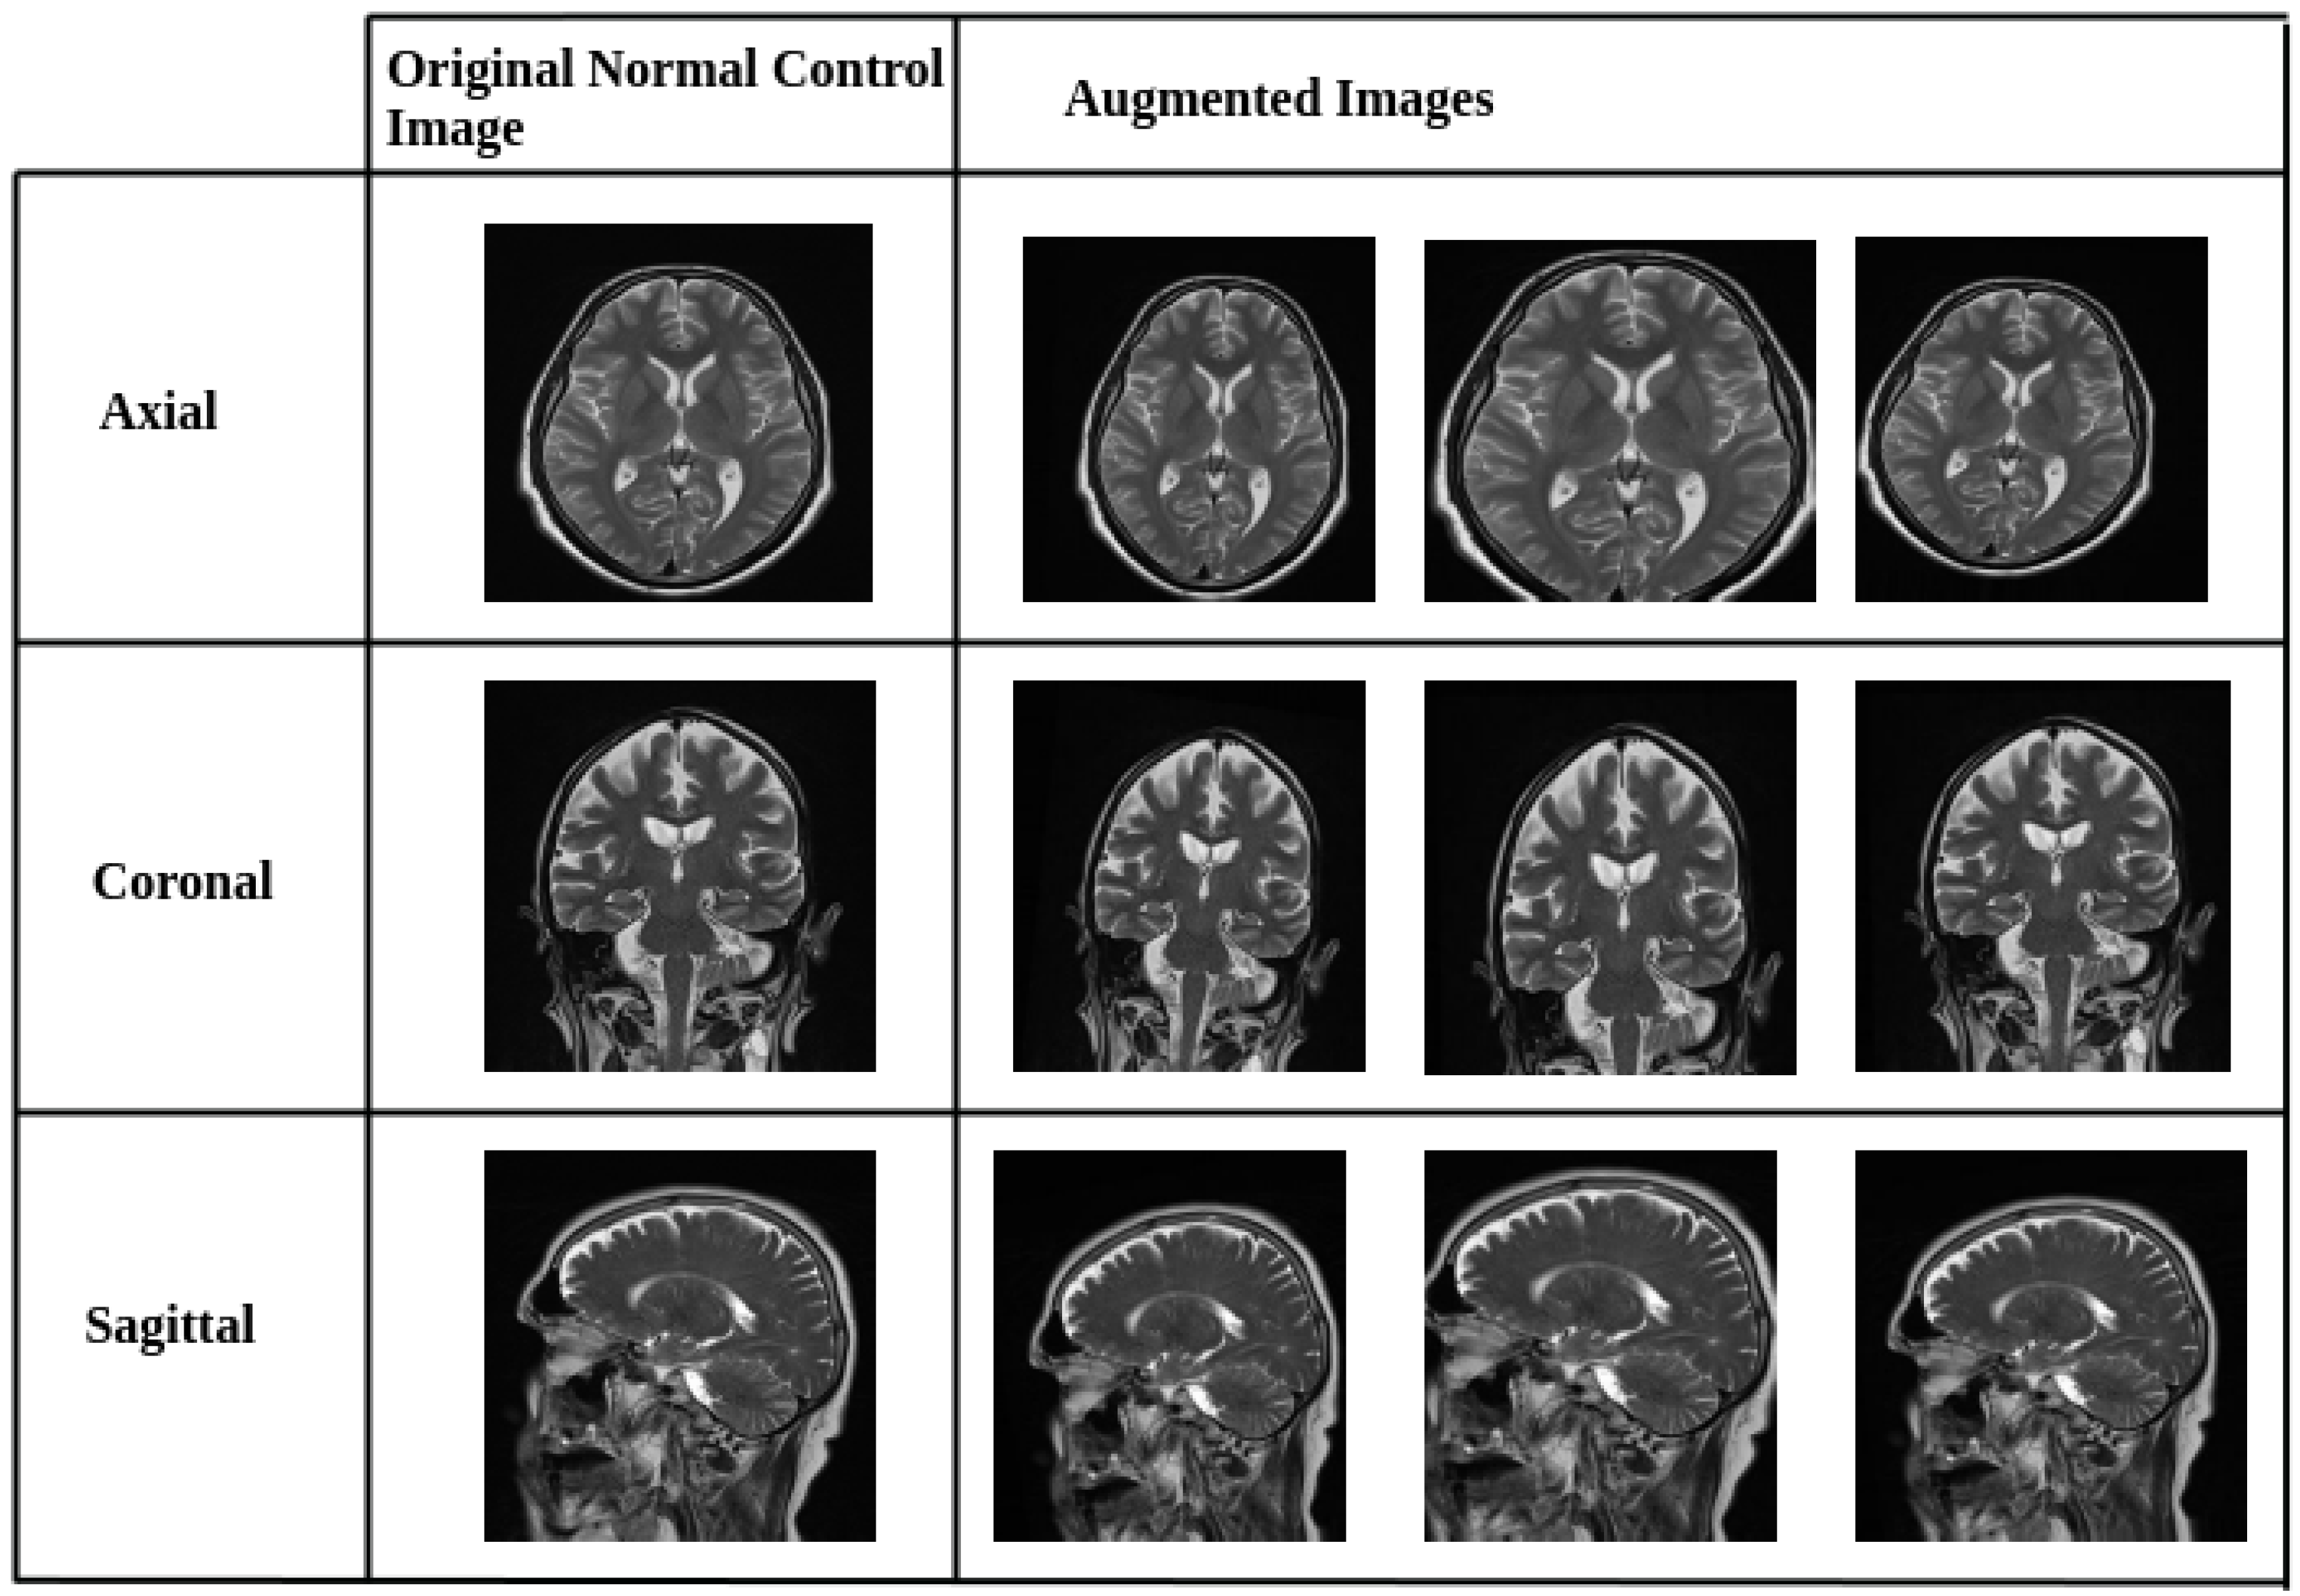

2.2. Data Preprocessing and Augmentation Strategy